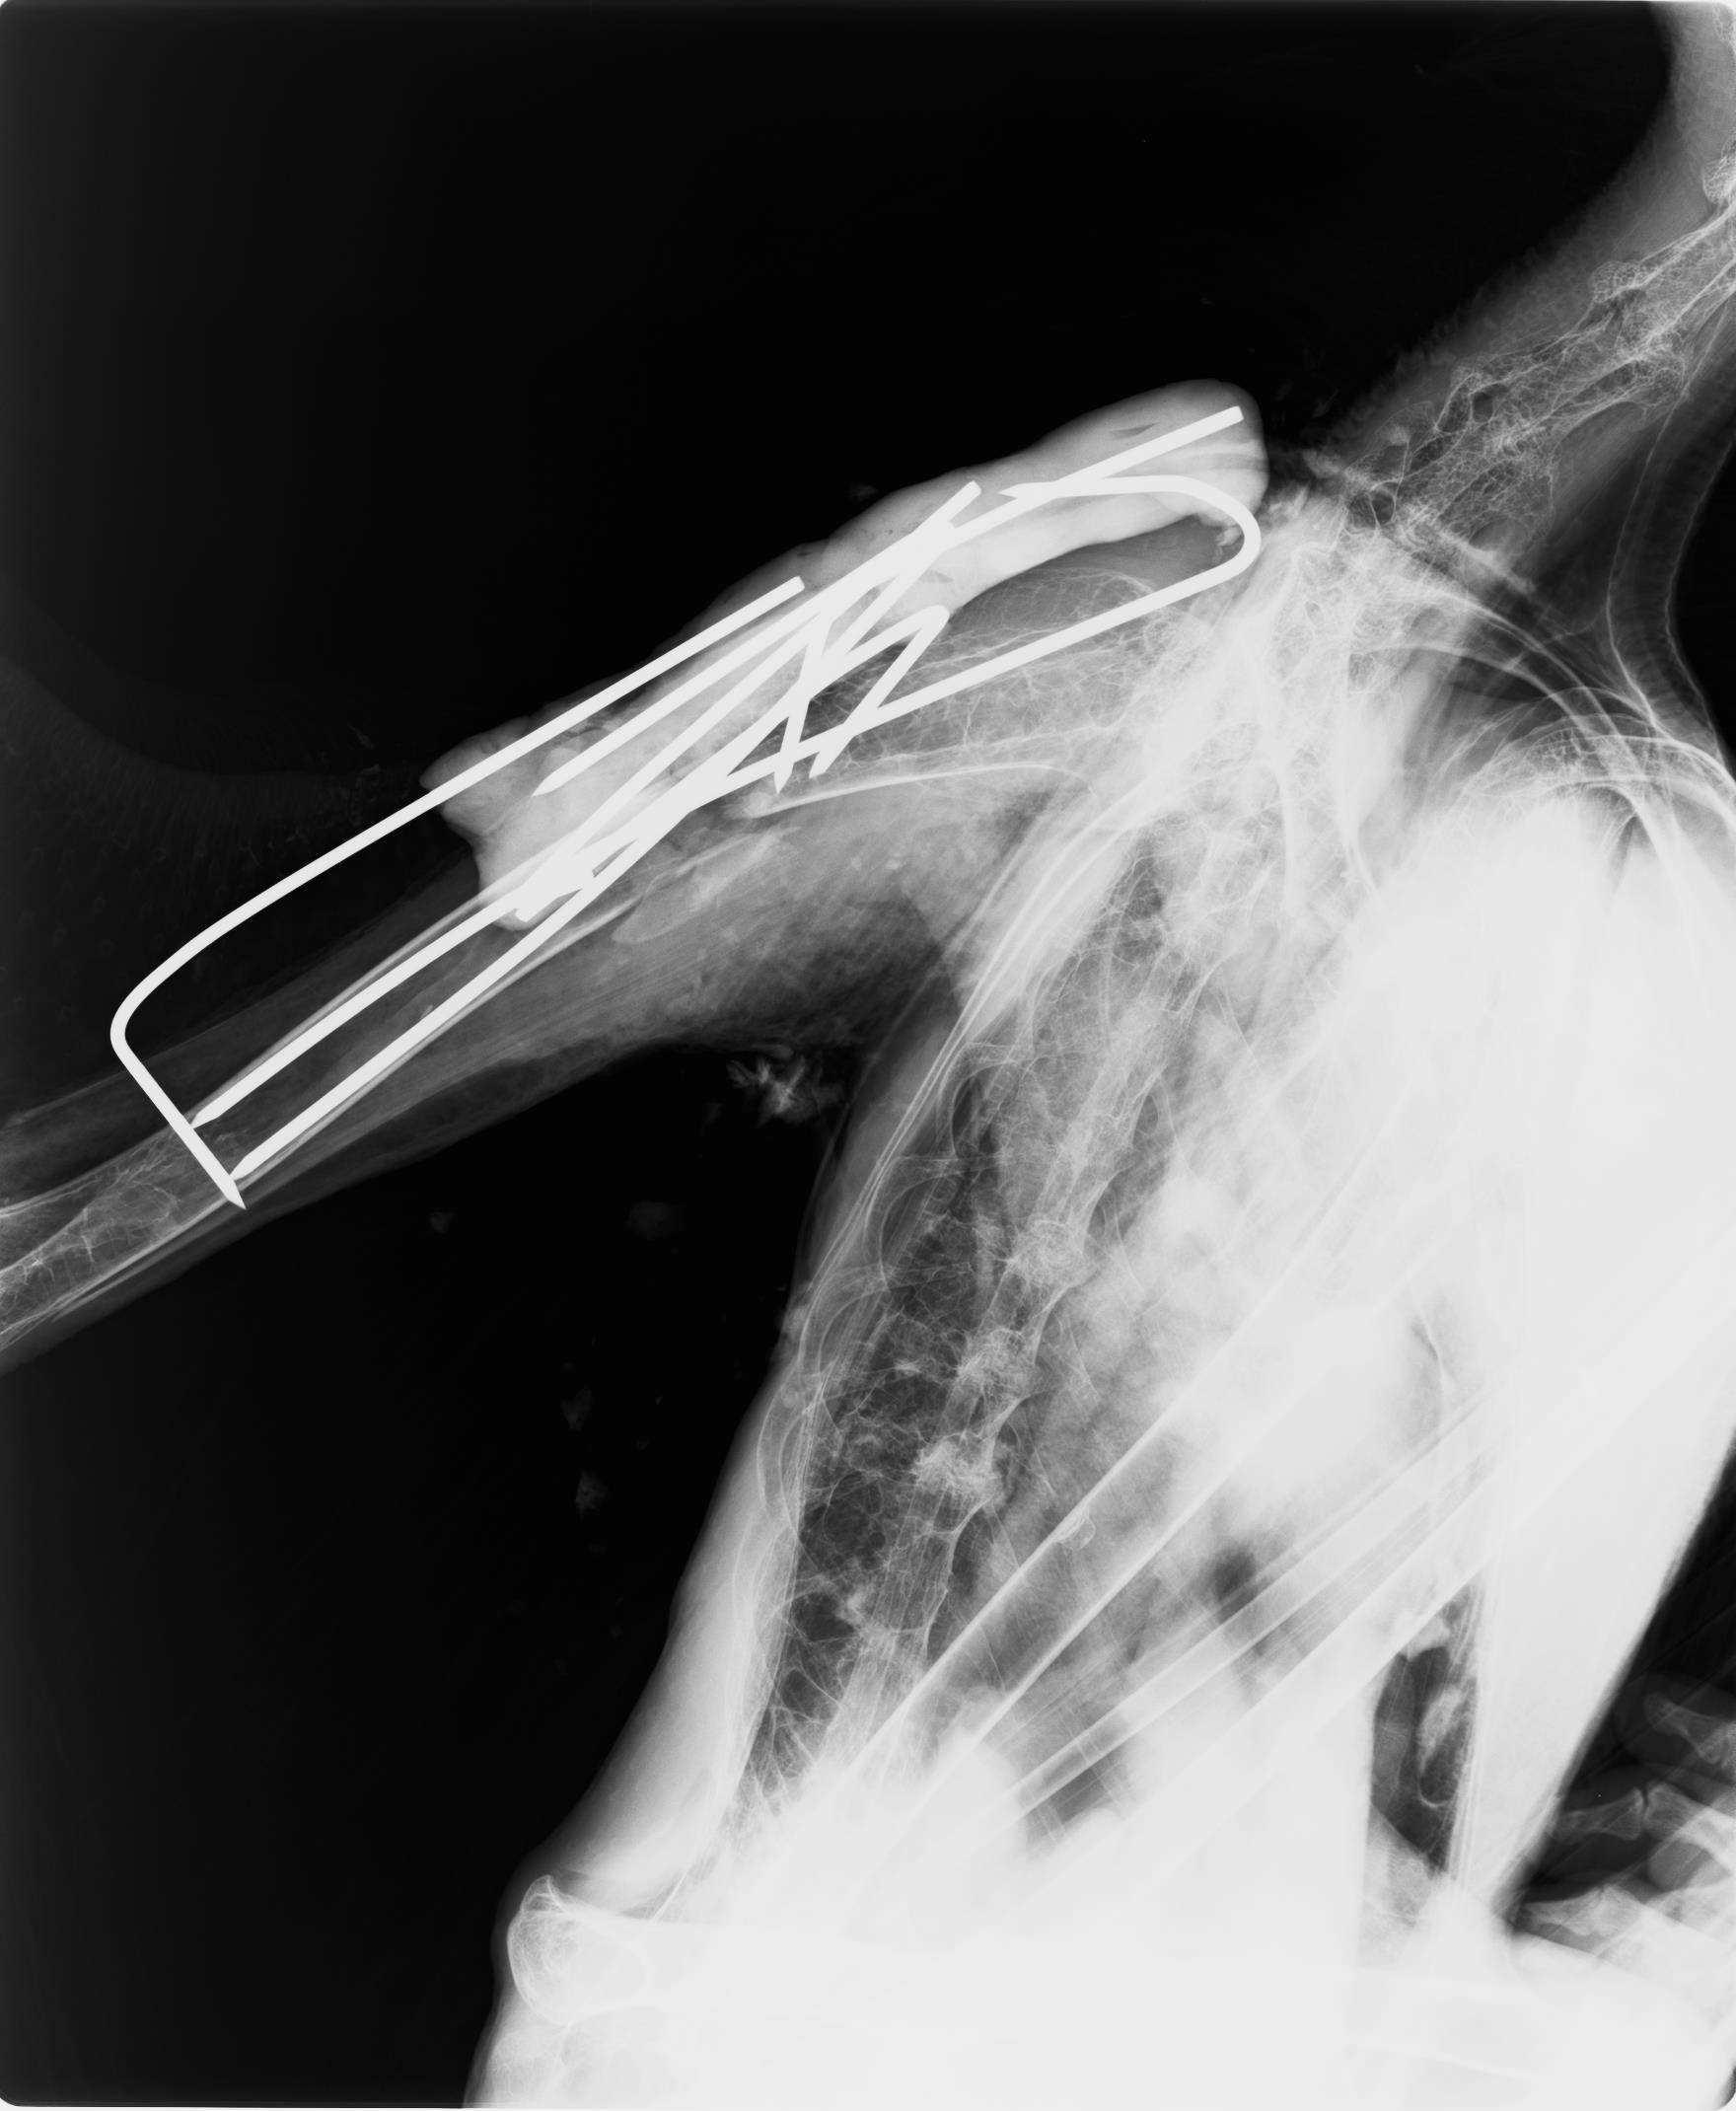

約1か月の療養の後、再び麻酔をかけて患部のレントゲンを撮影したところ、骨折した骨が十分にくっついたため、医療用のピンを外すことにしました。